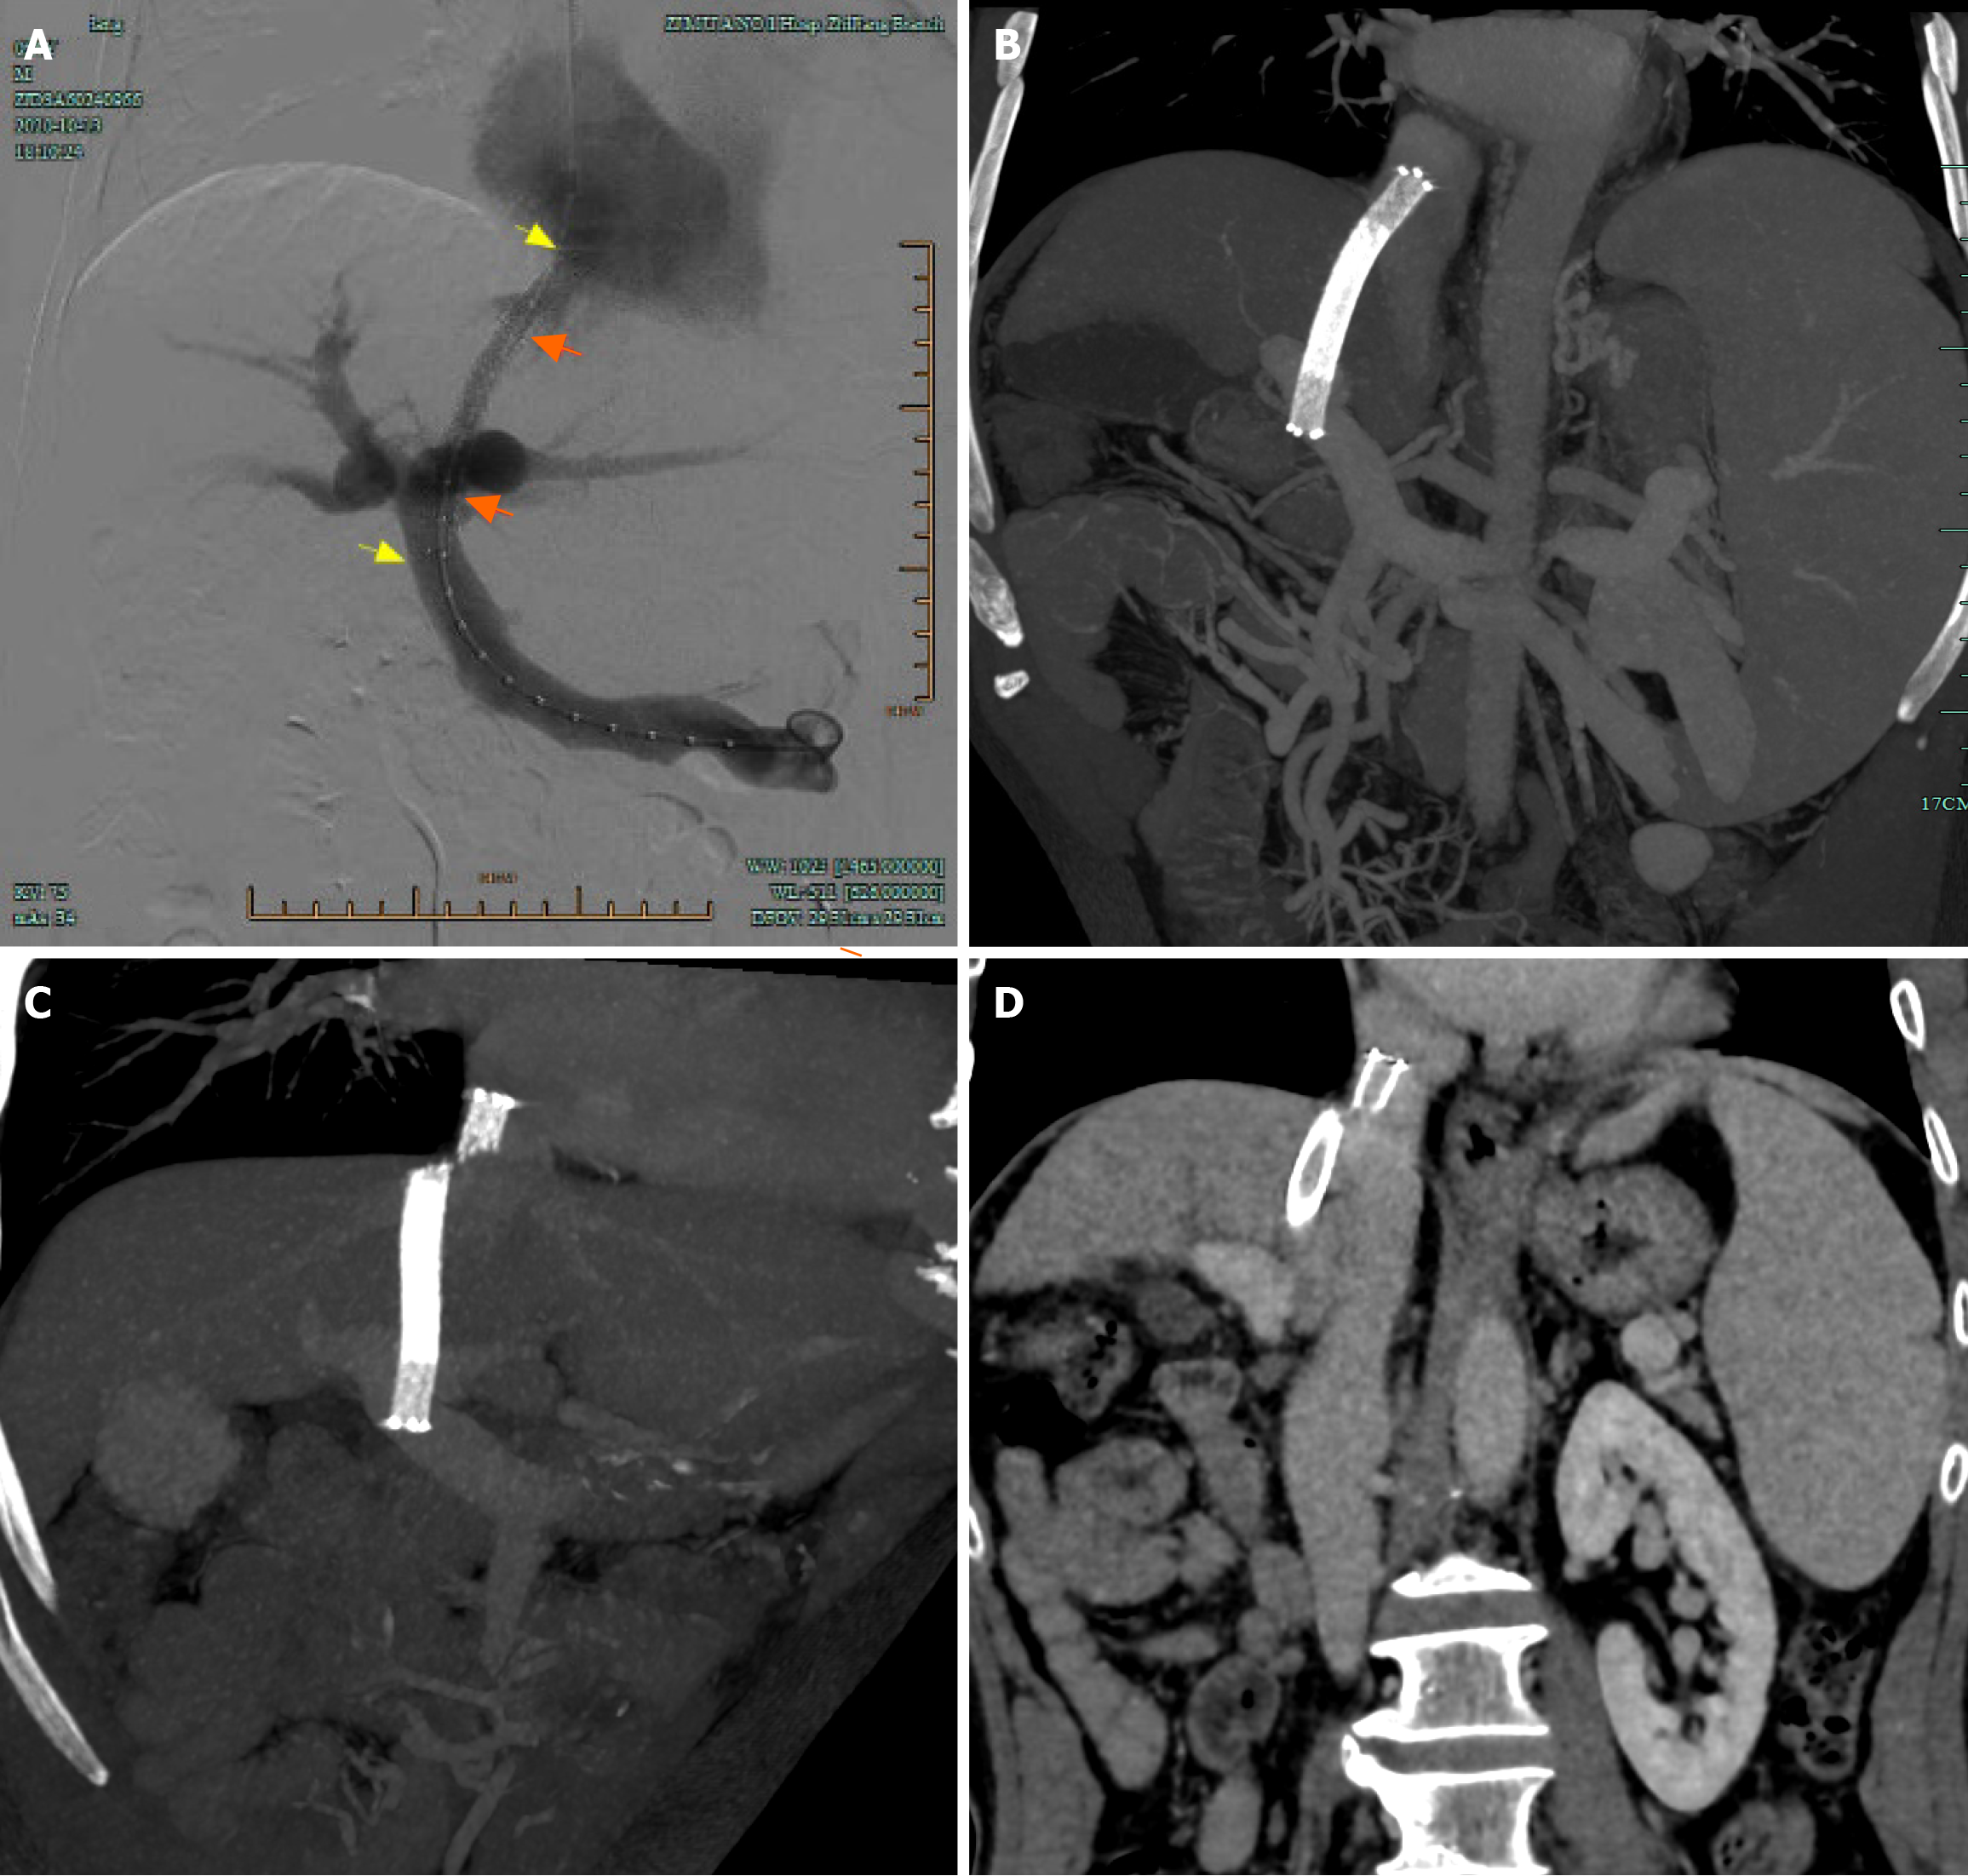

Following the procedure, melena disappeared immediately and the patient was transferred out on day 3. And the patient was advised to undergo follow-up liver CT angiography at 1 and 3 months postoperatively to assess shunt patency and monitor for the development of hepatocellular carcinoma. Subsequent evaluations should then be performed every six months thereafter. CT images one month after TIPS creation revealed metallic continuity of the stents (Figure 3B). However, follow-up CT imaging at 15 months post-procedure demonstrated stent fracture at the hepatocaval confluence (Figure 3C), although notably, the stent lumen remained patent (Figure 3D). A 20 mm stent fragment was radiologically confirmed to be lodged within the infra-diaphragmatic segment of the IVC, exhibiting positional stability without evidence of proximal migration toward the right atrium on serial imaging surveillance. The patient was treated conservatively as he was asymptomatic. CT images and color Doppler ultrasound 14 months after the procedure demonstrated neither further stent fracture nor further dislocation of the stent fragment. No symptoms associated with the stent fracture were observed for 15 months. However, the patient was readmitted 30 months post-TIPS due to recurrent esophagogastric variceal bleeding and ascites. Enhanced abdominal CT indicated occlusion of the original shunt (Figure 4). An attempt to revise the dysfunctional shunt via a stent-in-stent approach was conducted but was unsuccessful. Con

There is no consensus on the management of stent fractures. Treatment mainly depends on the type of stent fracture, clinical symptoms and potential risks[3,13]. Stent fracture can be classified as type I (no loss of stent integrity), type II (loss of stent integrity), and type III (separation or embolization of the fractured segment)[15]. Treatment of type I and type II stent fractures is typically performed using interventional procedures to insert a second stent to stabilize the fractured parts (stent-in-stent maneuver)[16]. However, surgery may be required to retrieve the distally migrated fragment in type III stent fractures, as the fragment can move into the right atrium, right ventricle and the pulmonary artery resulting in conduction abnormalities, valvular damage, perforation and possible death[17]. Fortunately, this rarely occurs. Komaki et al[13] reported a patient with a type III stent fracture after TIPS who was treated conservatively as he was asymptomatic for 15 months and follow-up CT images demonstrated neither further stent fracture nor further dislocation of the stent fragment. Two similar cases with type III stent fractures caused no acute mechanical complications and were managed conservatively[3,12]. In our case, the patient developed a type III stent fracture but the fragment did not migrate distally. He was treated conservatively as he was asymptomatic. Unfortunately, the patient was hospitalized due to recurrent esophagogastric variceal bleeding and ascites caused by shunt thrombosis 30 months later. Following failed attempts to recanalize the original shunt, a successful parallel TIPS was established via the proximal end of the fractured stent to decompress the portal venous system, effectively mitigating the variceal bleeding and ascites. Additionally, the anchoring effect of the newly implanted stent minimized the risk of stent fragment migration into the right atrium, right ventricle, and pulmonary artery. After parallel TIPS, the patient experienced no further episodes of bleeding or ascites, and is currently under follow-up observation.